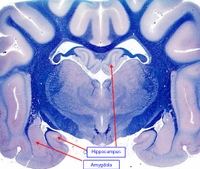

HIPOCAMPO: Es una estructura de la corteza cerebral con 3 capas de células, llamada ARQUEOCORTEX, de importancia en aprendizaje asociativo y memoria (particularmente memoria de corto tiempo). Tanto pacientes amnésicos como animales con daños en hipocampo exhiben problemas tiempo-dependientes en tareas de comportamiento generalmente descritas como asociativas o relacionadas por naturaleza. Este área del cerebro tiene un bajo umbral de ataques o convulsiones.

AMIGDALA: Es una región altamente diferenciada cerca del polo temporal de los hemisferios cerebrales de los mamíferos. Es un núcleo basal que está implicado en la emoción, memoria, comportamiento social, comportamiento reproductor, miedo y agresión, y modulación de sistemas autonómicos y neuroendocrinos. Muchos de sus efectos son opuestos a los del septum. Lesiones de la amígdala pueden suponer comportamiento dócil, mientras que su estimulación produce comportamiento agresivo.